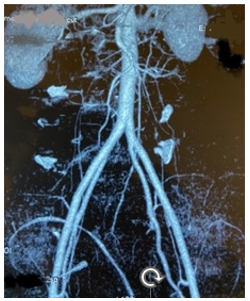

A CT scan of the lumbar spine revealed anterolisthesis of L5 on S1, which was classified as Meyerding grade III with bilateral isthmic lysis of L5 (Figure 1). An angioscan of the iliac vessels was performed to assess the level of bifurcation of the iliac vessels (Figure 2).

Figure 2: Angioscan of the iliac vessels